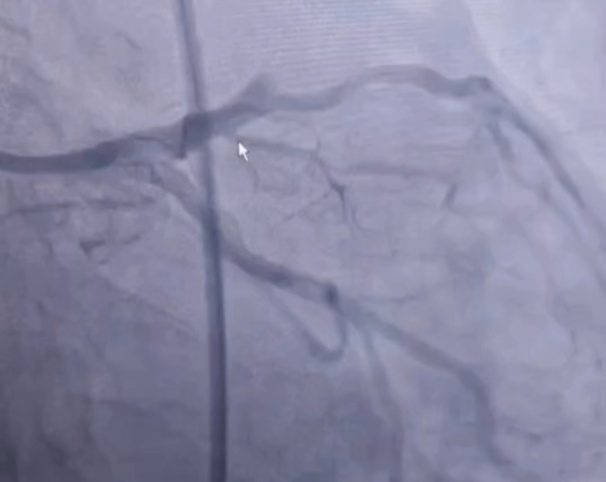

在患者家属的积极配合下,在患者心跳恢复后,立刻启动了导管室。在这关键时刻,导管室医护团队早已准备充分,18:47患者转运至导管室并已完成术前准备,郑凯和钍戈医生在全麻及呼吸机、临时起搏器保驾护航下,行急诊介入治疗,19:04造影结束,19:45手术结束,成功开通闭塞病变血管!

术前示前降支近段闭塞 | 开通前降支罪犯病变后 |